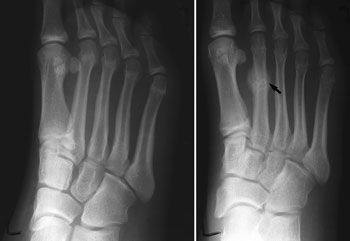

X-rays. X-rays provide images of dense structures, such as bone. Since a stress fracture starts as a tiny crack, it is often difficult to see on a first x-ray. The fracture may not be visible until several weeks later when it has actually started to heal. After a few weeks, a type of healing bone calledcallus may appear around the fracture site. In many cases, this is the point at which the fracture line actually becomes visible in the bone.

A00379F02.jpg" title="(Left) This x-ray of a patient who reported pain in the second metatarsal does not show an obvious stress fracture. (Right) Three weeks later, an x-ray of same patient shows callus formation at the site of the stress fracture." credit="">Other imaging studies. If your doctor suspects a stress fracture but cannot see it on an x-ray, he or she may recommend a bone scan or a magnetic resonance imaging (MRI) scan. Although a bone scan is less specific than an MRI in showing the actual location of the stress fracture, both of these types of studies are more sensitive than x-rays and can detect stress fractures earlier.

(Left) This x-ray of a patient who reported pain in the second metatarsal does not show an obvious stress fracture. (Right) Three weeks later, an x-ray of same patient shows callus formation at the site of the stress fracture.